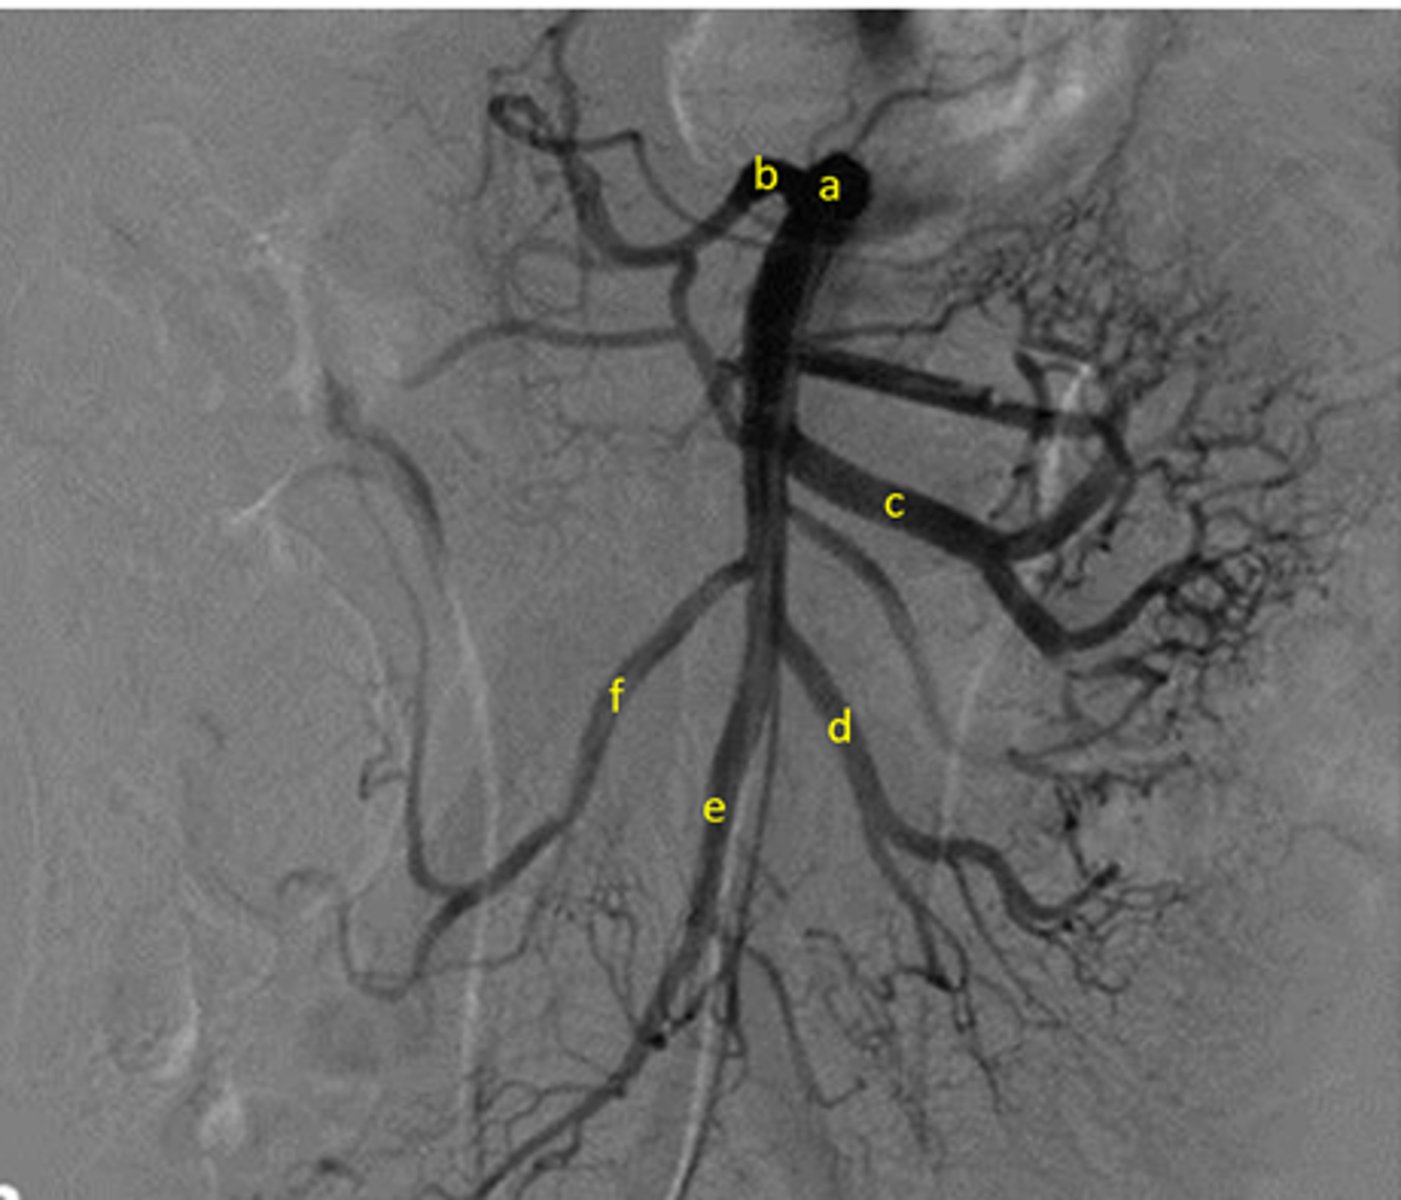

New cards

Identify pertinent anatomy of the following radiograph

A: SMA

B: Middle Colic

C:Jejunal arteries

D: Ileal arteries

E: Iliocolic

F: Right colic

<p>A: SMA</p><p>B: Middle Colic</p><p>C:Jejunal arteries</p><p>D: Ileal arteries</p><p>E: Iliocolic</p><p>F: Right colic</p>